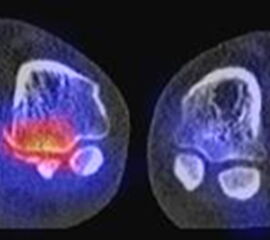

Abbildung 1.8.a und b: Akute Arthritis bei bekannter Gicht in beiden OSG: links die Früh-/Weichteilphase; rechts die Mineralisations­phase. Deutliche, entzündlich bedingte Mehranreicherungen in der Früh-/Weichteilphase. In der Mineralisation­sphase erkennt man die entzündliche Mitreaktion der subchondralen Gelenkabschnitte.

Abbildung 1.8.c - e: Akute Arthritis in beiden OSG, rechts > links. Im SPECT/CT erkennt man die Mitreaktion der subchondralen Gelenkabschnitte. Die Arthritis ist so akut, dass (noch) keine ossären morphologischen Veränderungen im CT abgrenzbar sind.

Zum Lesen der Bildbeschreibung und zur Vollansicht bitte die Bilder anklicken. Bilder: H. C. Rischke